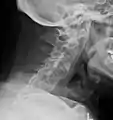

X-rays

The earliest changes demonstrable by plain X-ray shows erosions and sclerosis in sacroiliac joints. Progression of the erosions leads to widening of the joint space and bony sclerosis. X-ray spine can reveal squaring of vertebrae with bony spur formation called syndesmophyte. This causes the bamboo spine appearance. A drawback of X-ray diagnosis is the signs and symptoms of AS have usually been established as long as 7–10 years prior to X-ray-evident changes occurring on a plain film X-ray, which means a delay of as long as 10 years before adequate therapies can be introduced.[24]